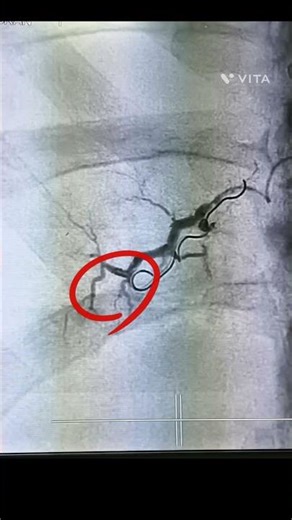

Arteriovenous Malformation (AVM)